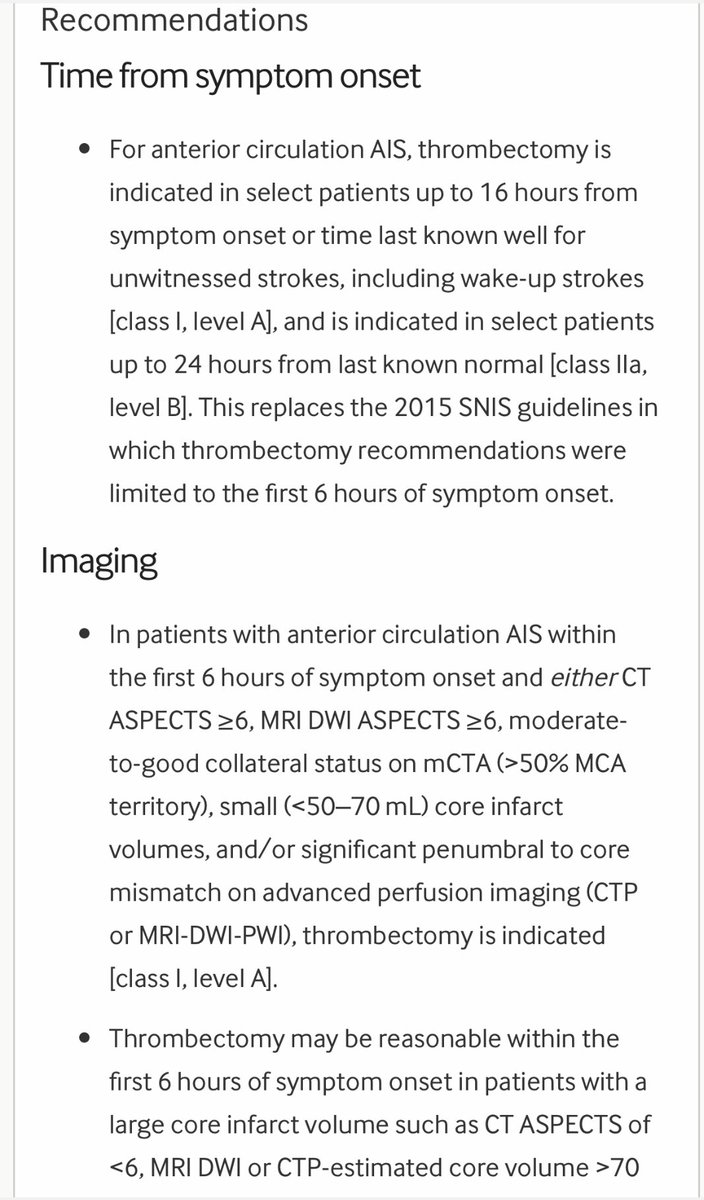

♦️قسطرة تداخليه لسحب الجلطه من الشرايين الرئيسيه ان وجدت

(فقط اول ٦ ساعات قد تمتد بشروط)

♦️قسطرة تداخليه لسحب الجلطه من الشرايين الرئيسيه ان وجدت

(فقط اول ٦ ساعات قد تمتد بشروط)

🧠خيارات علاج السكته الدماغيه في اول ٦ ساعات

youtu.be

💥فيديو توعوي

🧠خيارات علاج السكته الدماغيه في اول ٦ ساعات